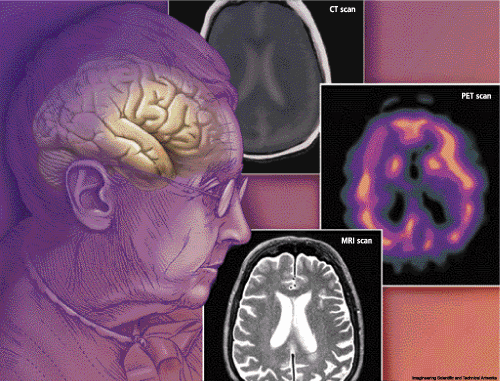

What is so disappointing about the government’s National Dementia Strategy which has just been announced is that it sadly fails to support much needed research into dementia.

There is no light at the end of the tunnel for those suffering from dementia. One day it could be us. Yet amazingly The Alzheimer’s Research Trust receives no government funding and relies on donations to fund its vital research.

Every 14 minutes another person is diagnosed with Alzheimer’s in England and Wales. What is the point of having memory clinics in every town if there are no new drugs to treat those inflicted with this horrid disease? Why couldn’t the government have invested half of the £150 million from this strategy for research into dementia?